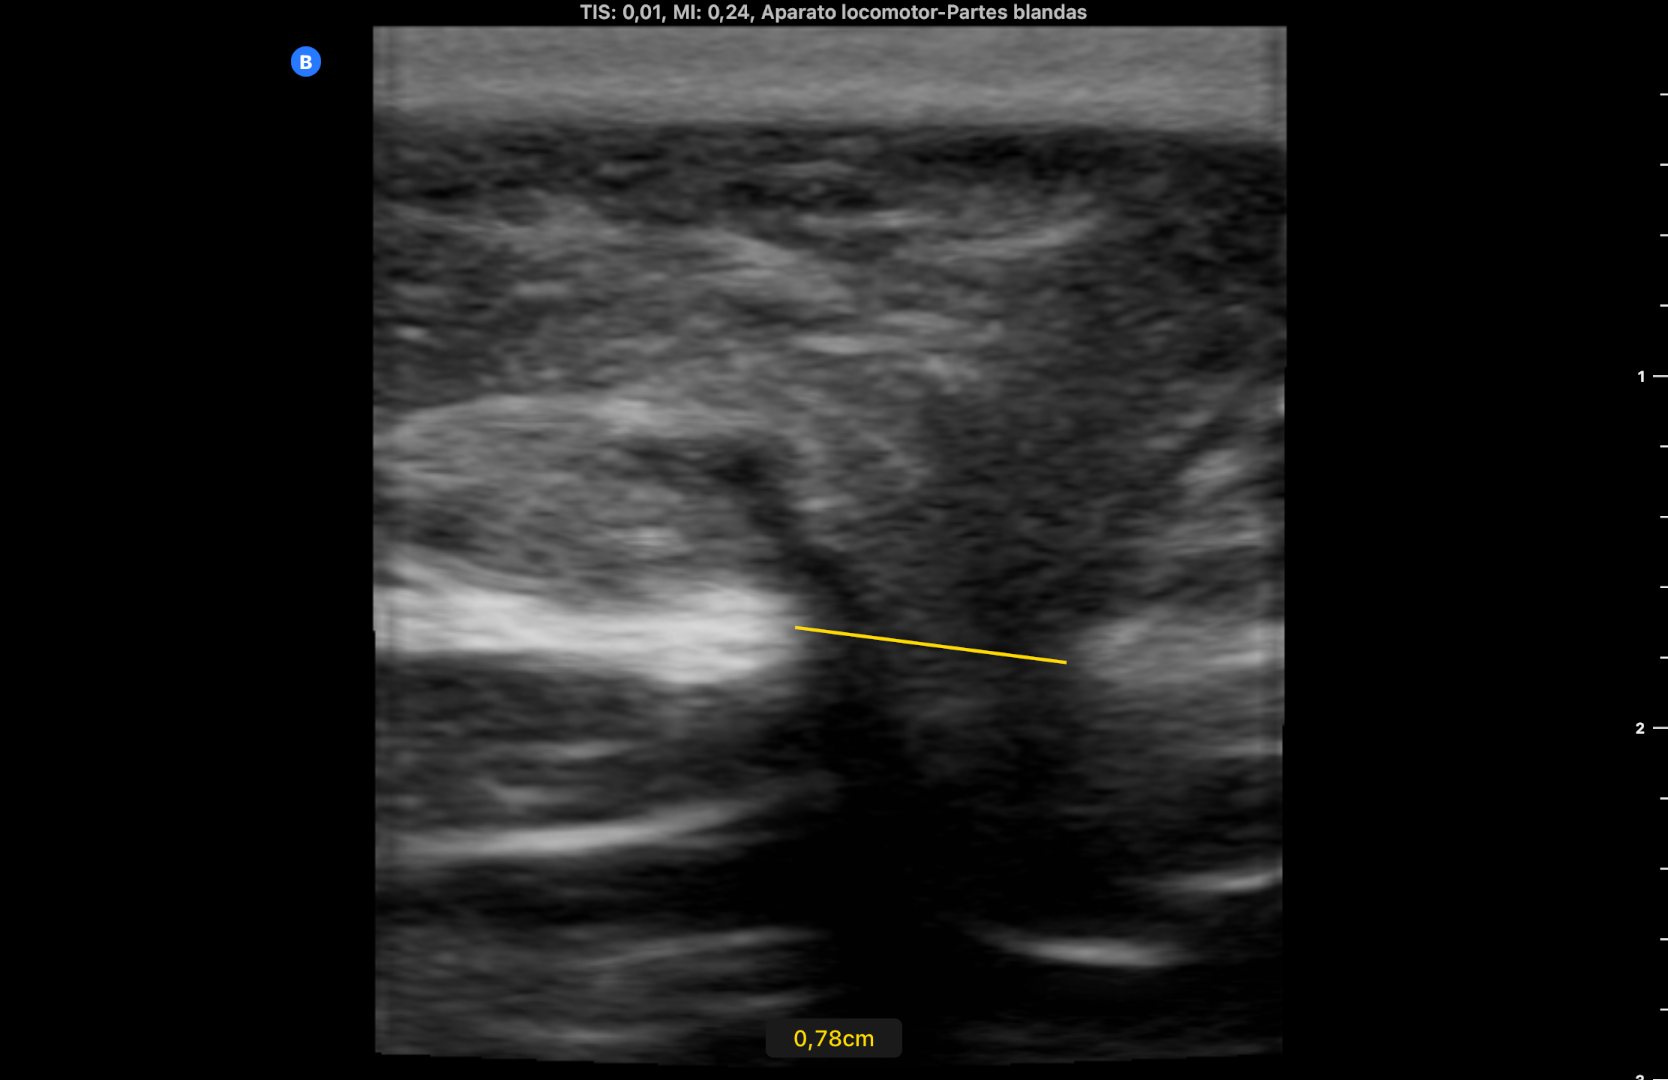

Se derivó al Servicio de Cirugía General por circuito preferente, advirtiendo de acudir a Urgencias si volvía a aparecer el bulto y el dolor. Se citó 6 días después persistiendo el orificio herniario de 7,8 mm sin extrusión de asa intestinal (imagen 3).